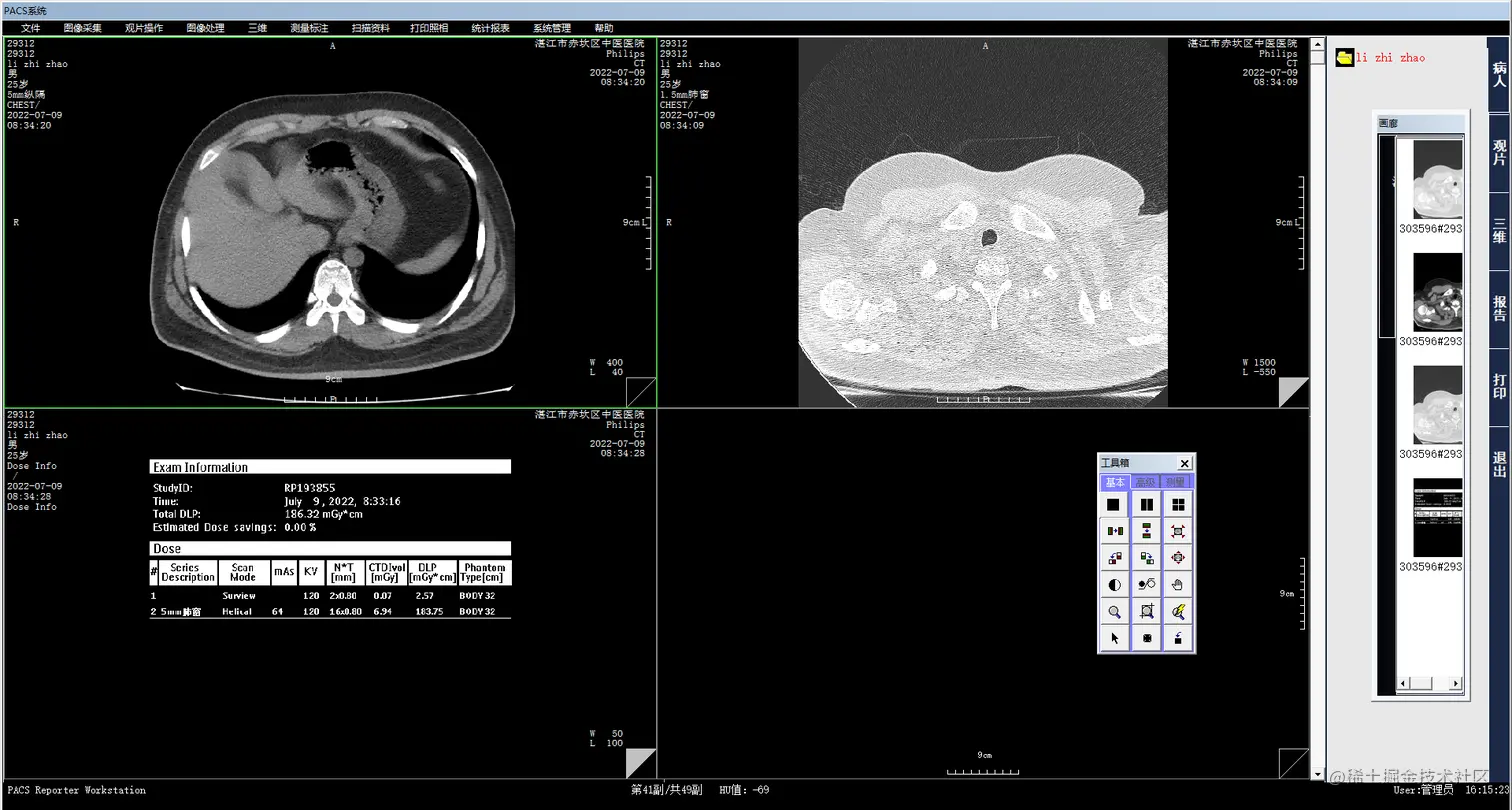

MIP(Maximum Intensity Projection),最大密度投影,最大密度投影是将一定厚度(即CT层厚) 中最大CT值的体素投影到背景平面上,以显示所有或部分的强化密度高的血管和(或)器官。

MIP的灰阶度反映CT值的相对大小,且比较敏感,即使小的差异也能被检测,如钙化灶、骨骼CT值非常高,充盈对比剂的血管同样很高的CT值,但总是低于钙化灶和骨骼,在MIP图像上,其明亮度不一样,可区分。    应用:广泛应用于具有相对高密度的组织和结构,如显影的血管、骨骼、肺部肿块以 及明显强化的软组织病灶等,对于密度差异甚小的组织结构以及病灶则难以显示。